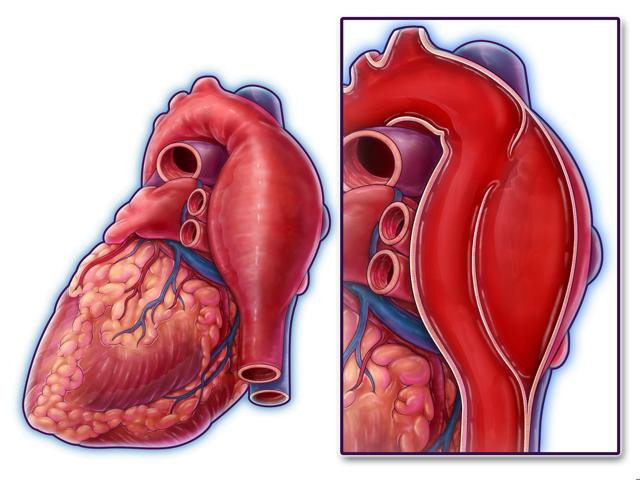

Sırrı Süreyya Önder’in geçirdiği aort diseksiyonu, halk arasında bilinen adıyla ana atardamar yırtılması, toplumda sık görülmeyen ancak hayati tehlikesi yüksek bir kalp damar hastalığına dikkat çekti.

Aort diseksiyonu yani ana atardamarda yırtılmanın, kalp cerrahisinin karşılaştığı en acil durumlardan biri olduğunu belirten Prof. Dr. Köksal, bu hastaların ancak yarısının hastaneye ulaşabildiğini, ameliyat olanların ise yalnızca yarısının hayatta kalabildiğini ifade etti.

"Bu yırtıkların temelinde genellikle aortada genişleme yani anevrizma ile birlikte kontrolsüz yüksek tansiyon yer alır.Sırrı Süreyya Önder örneğinde olduğu gibi, daha önce 4.7 cm gibi sınırda ölçülen bir aort çapınız varsa ve kontrolsüz yüksek tansiyonunuz mevcutsa, risk çok yüksektir” dedi.

Yırtığın kalpten çıkan ana damarda başladığını ve aşağı inerek kalbi besleyen damarları tıkayabileceğini belirten Prof. Dr. Köksal, şu bilgileri verdi:

“Sırrı Süreyya Önder’in kalp krizi geçirmesinin nedeni sağ koroner damarının bu yırtık nedeniyle tıkanmasıydı.Yırtık yukarıya çıktığında ise beyne giden kan azalabilir, bu da bayılma şikâyetleriyle kendini gösterebilir. Bu durum, hayati tehlikenin çok yüksek olduğunu gösterir.”